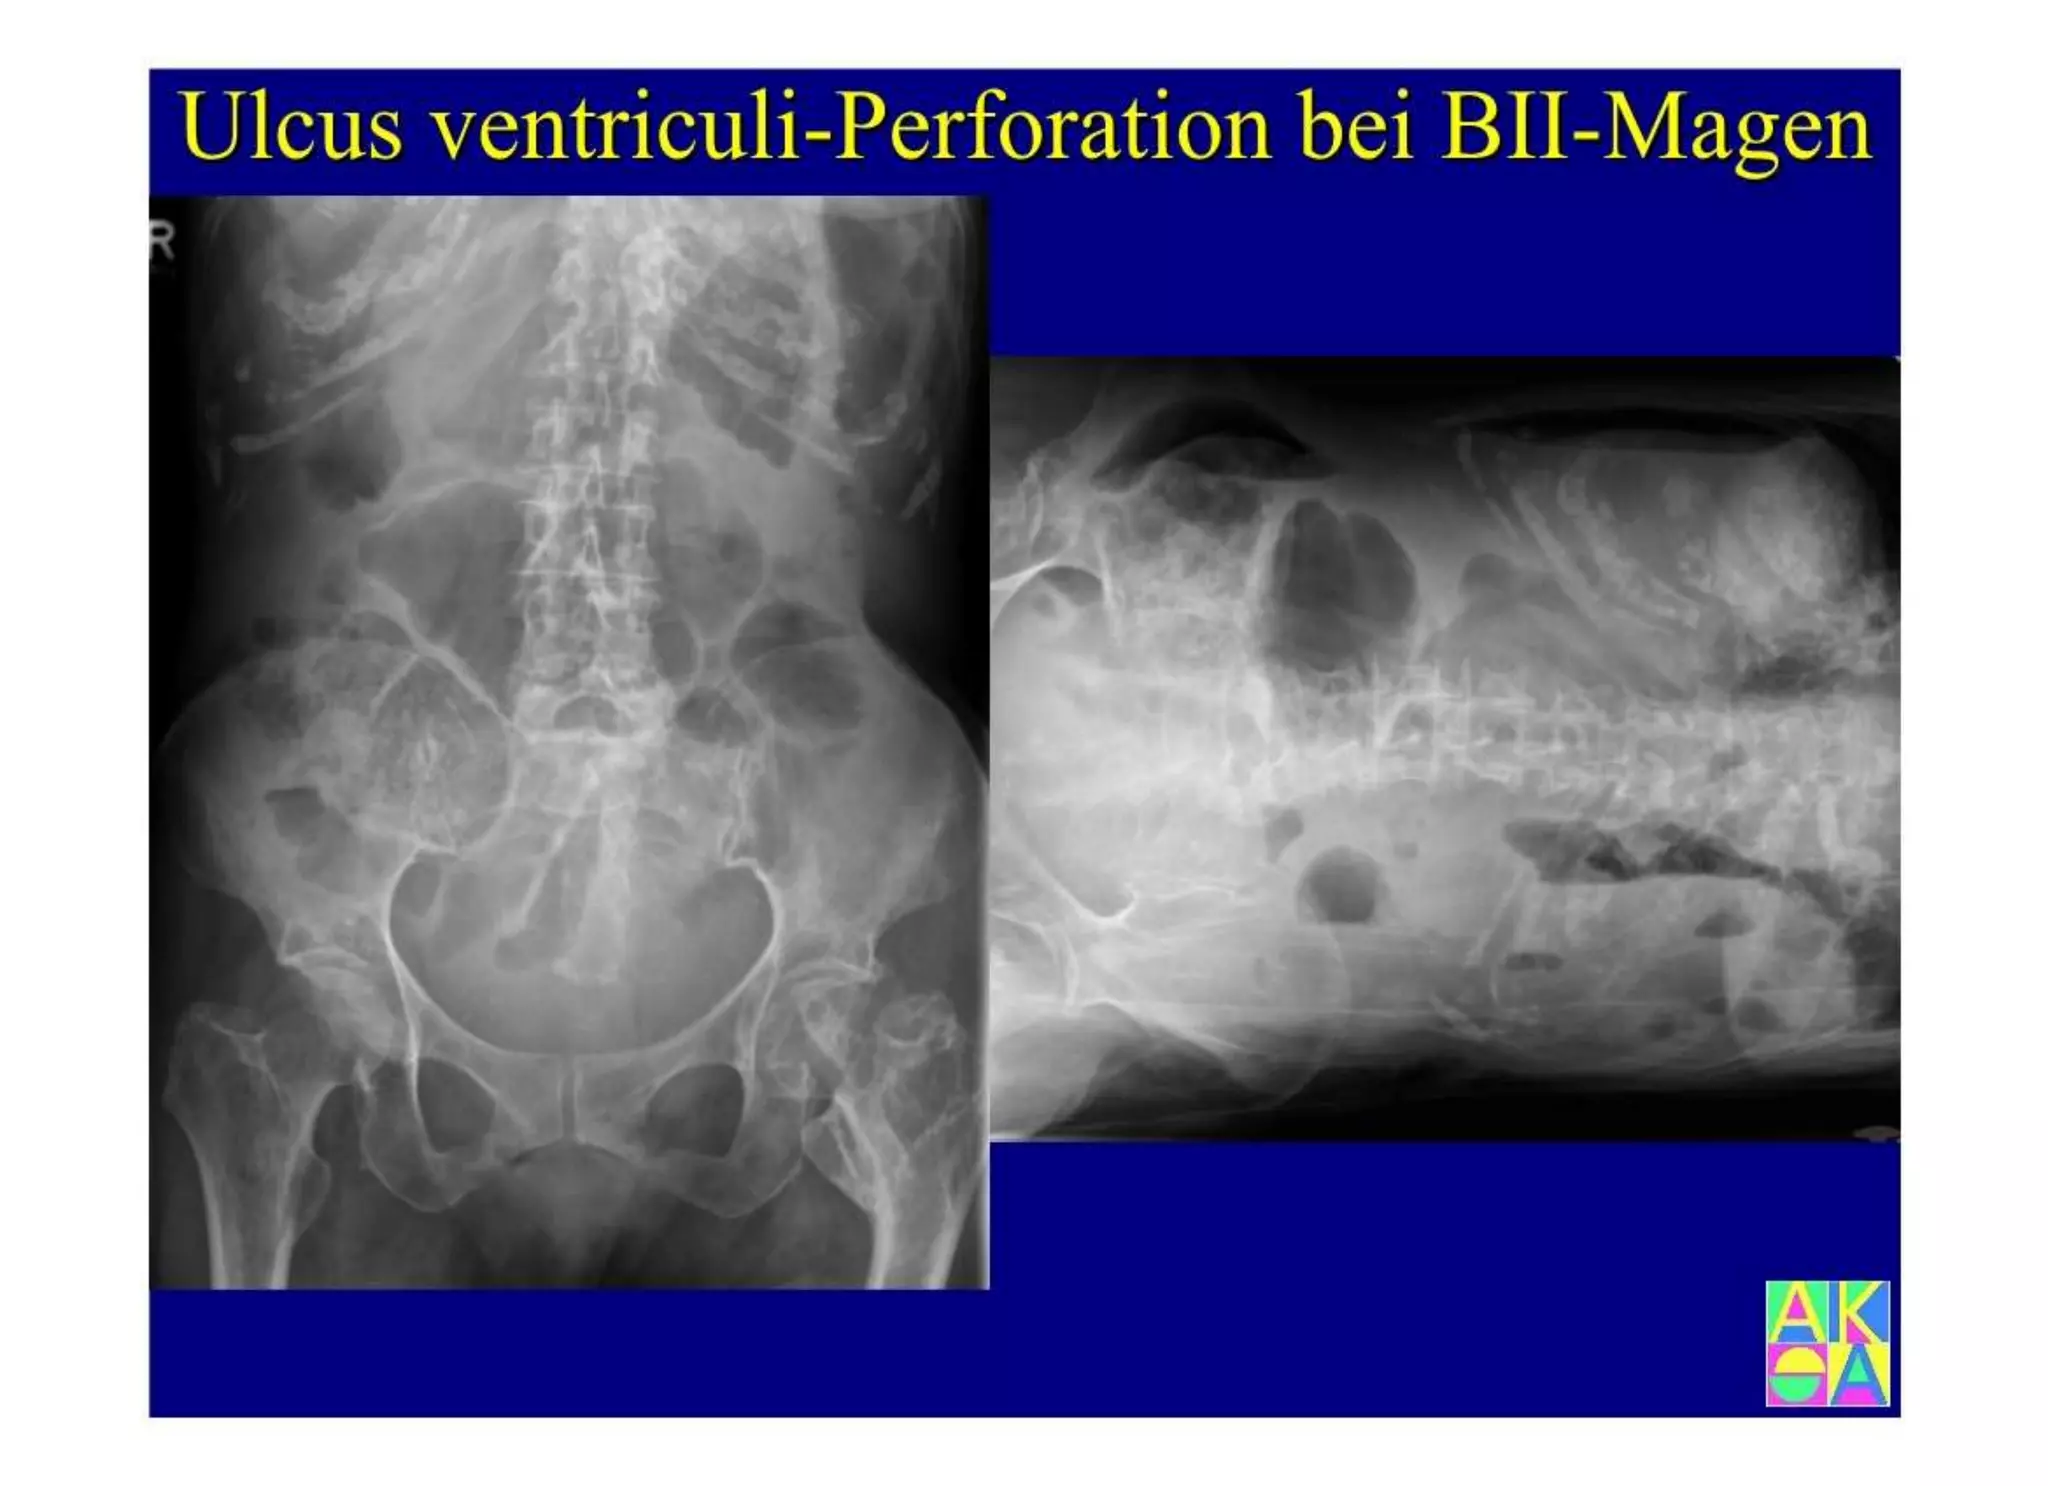

Chronische Enteropathie und Ileus, Dünndarm und Dickdarmdiagnostik, Mechanischer und paralytischer Ileus, Eingeklemmte Darmabschnitte, aufgereihter Bridenileus, und dazu Dickdarmileus, eingeklemmte Hernien, Weitergabeskript